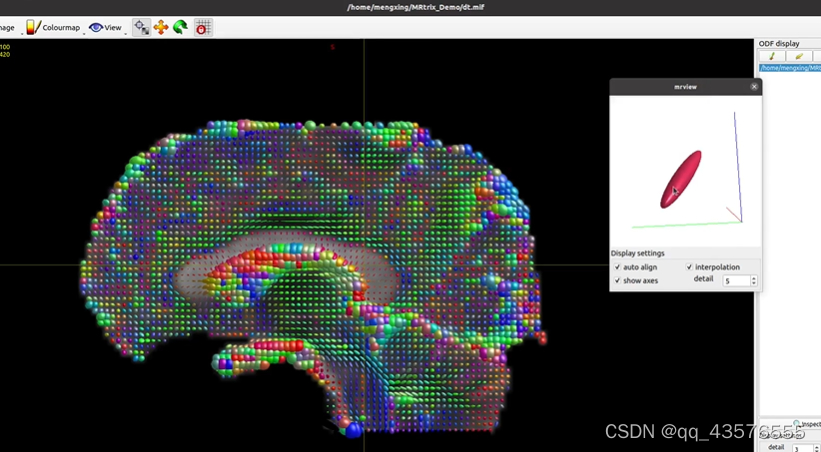

maskfilter: [100%] applying dilate filter to image -生成弥散张量dt.mif,可用mrview查看,每个体素有六个值(描述一个椭圆体),标志着水分子的弥散方向,用椭球方向标志纤维的走向,用FA值衡量各向异性,各向异性越大,FA值越大

tensor2metric: [100%] computing metrics由于弥散像体素比纤维大得多,无法反映神经纤维束的真实走向,这里我们不用dt.mif估算神经的方向,因此使用constrained spherical deconvolution(CSD)算法,计算各个方向纤维束的贡献,这里的kernel称为反应函数